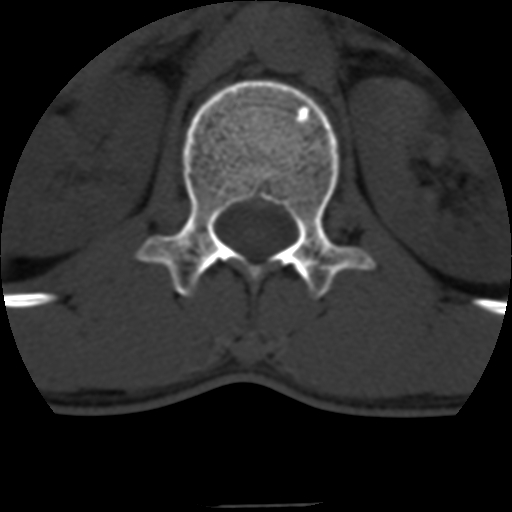

标题: CT10387:男,31岁,胸腰段CT [打印本页]

男,31岁,从6米高处坠落伤两天,腰背部疼痛,临床要求ct扫描胸10-腰1。请大家帮忙看看骨质有问题吗?

t12、l1锥体前缘轻度楔形变,平扫示椎体前缘骨小梁欠规整,第9幅图示椎体前缘骨质不连续,结合外伤史考虑椎体轻度压缩骨折。

楼主扫描层厚可能较大,每个椎体只有三个层面.

从所示层面分析,无明确骨折征象,象类似病人我个人会建议mri除外骨挫伤.

从上查骨窗第九片椎体前缘皮质显示断裂.压缩骨折?